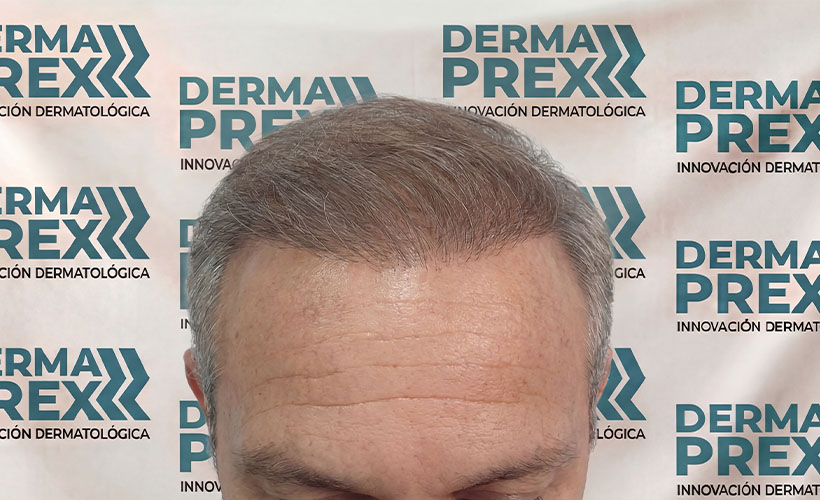

Resultados reales, confianza real

Cada tratamiento capilar cuenta una historia… y estas son las que más nos inspiran.

En esta sección encontrarás casos reales de personas que decidieron dejar de improvisar y empezar un tratamiento adecuado para su tipo de caída, logrando mejoras visibles en el crecimiento, fortalecimiento y salud de su cabello.